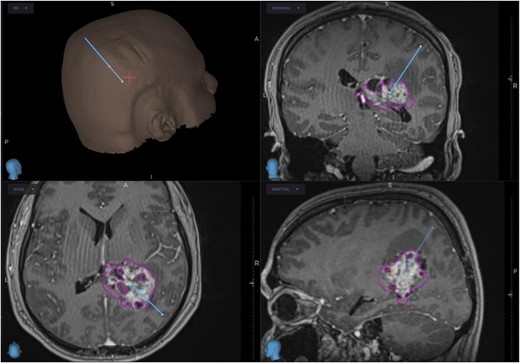

The patient was started on oral dexamethasone, resulting in the improvement of his headaches. The differential diagnosis based on imaging findings included an atypical meningioma, central neurocytoma, choroid plexus papilloma or carcinoma, ependymoma or an oligodendroglioma. He underwent a right parietal craniotomy with gross total resection of the lesion. Intraoperatively, use of the Vycor™ ViewSite Brain Access System (VBAS) was utilized, which allowed for optimized surgical site access, and reduced the risk of brain retractor injury to surrounding structures, namely the precentral gyrus. This was combined with intraoperative ultrasound (Fig. 3), which provided real time imaging and guided the extent of the resection. In addition, neuromonitoring and neuronavigation (Fig. 2) were incorporated to further reduce the risk of damage to surrounding structures. As part of the neuromonitoring, motor evoked potentials (MEPs) were performed to identify the precentral gyrus prior to insertion of the VBAS (Fig. 4), ensuring that any resection occurred posterior to the motor strip. During surgery, it was noted that the lesion was haemorrhagic and easily friable, with evidence of a previous recent haemorrhage.

Planned trajectory for excision of the tumour, as seen on the neuronavigation system.